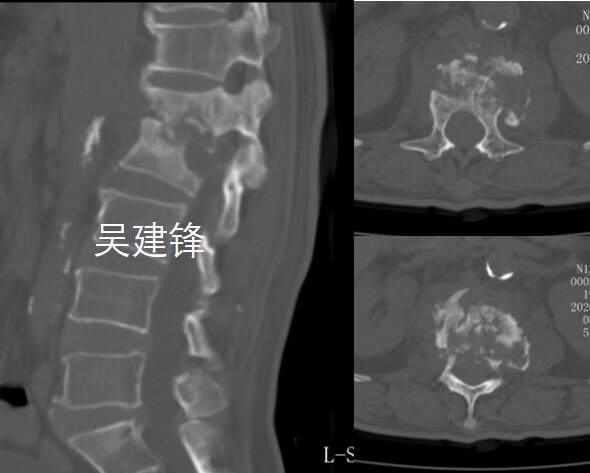

脊柱结核ct

脊柱结核ct,脊柱ct

脊柱结核

脊柱结核的ct及mri诊断影像天地

一例严重的脊柱结核伴后凸畸形的手术治疗